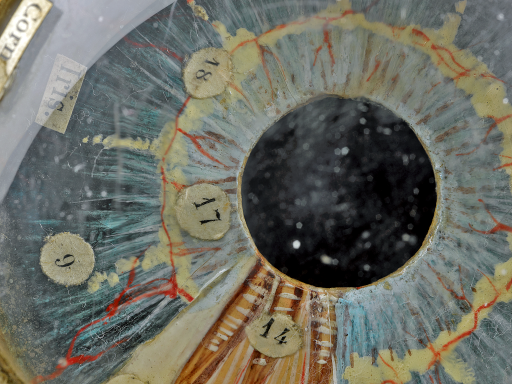

Assistant Curator Jack Mitchell explores how the Atlas of Ophthalmoscopy helped increase our understanding of the human eye